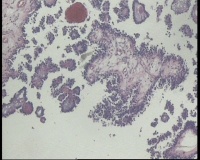

| 一般病史 | 彩超:盆腔可见囊实性回声,囊性为主,大小约5.0x3.7厘米,其内可见分隔回声,部分分隔内回声不纯净,形态欠规整 | ||||

| 标本名称 | 腔镜下右侧卵巢囊肿手术 | ||||

| 大体所见 | 囊壁样组织5.5x5.0厘米,4.5x2.5厘米2块,壁厚0.1-0.2lm,囊壁大部分光滑,局灶见0.7x0.5x0.3厘米淡黄色突起组织,另见淡黄色、肉粉色质软组织2.8厘米一堆。 | ||||